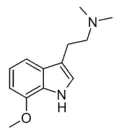

Substituted tryptamines, or serotonin analogues, are organic compounds which may be thought of as being derived from tryptamine itself. The molecular structures of all tryptamines contain an indole ring, joined to an amino (NH2) group via an ethyl (−CH2–CH2−) sidechain. In substituted tryptamines, the indole ring, sidechain, and/or amino group are modified by substituting another group for one of the hydrogen (H) atoms.

| Chemical structure | Short Name | Origin | Ring Substitution | RN1 | RN2 | Full Name | CAS Number |

|---|---|---|---|---|---|---|---|

| 5-MeO-DMT | Animals, plants | 5-OCH3 | CH3 | CH3 | 5-methoxy-N,N-dimethyltryptamine | 1019-45-0 |

| 6-Methoxy-DMT | artificial | 6-OCH3 | CH3 | CH3 | 6-methoxy-N,N-dimethyltryptamine | 2426-88-2 |